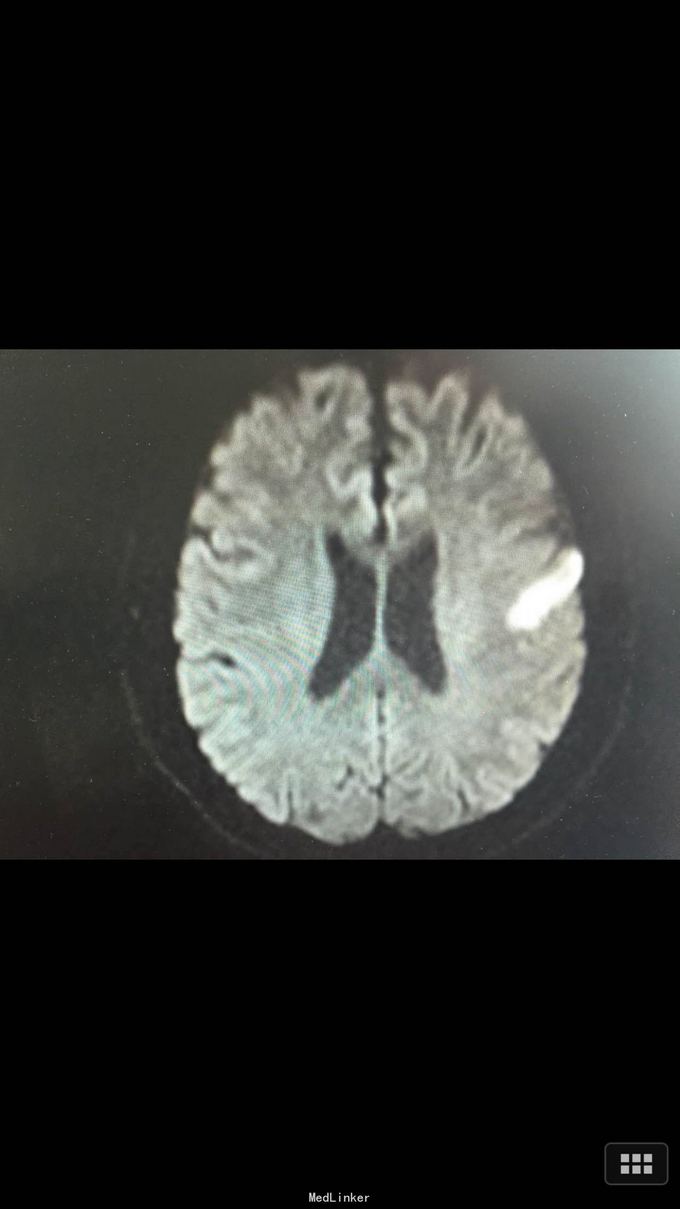

查体:BP:140/100mmHg,心肺腹无异常,神志清醒,完全运动性失语,右侧中枢性面瘫,四肢肌力、肌张力正常,腱反射正常,巴氏征R-L-,左足弓形足。 化验:血糖:14.3mmol/l,血脂:总胆固醇:13.29mm0l/l,LDL:6.6mmol/l,甘油三酯:24.51mmol/l。 影像学: